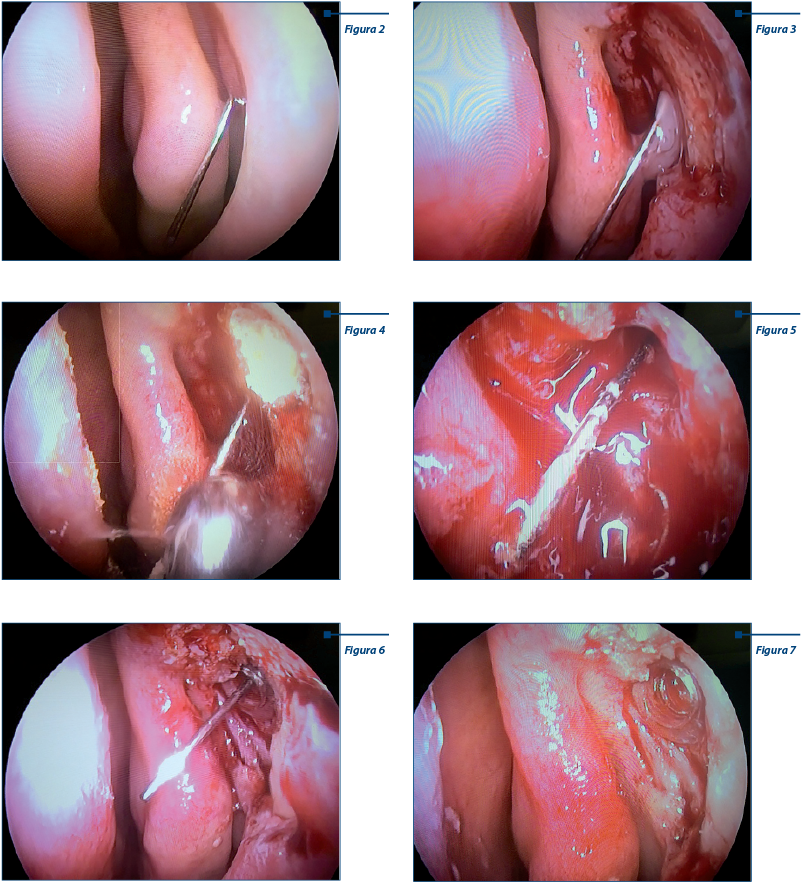

La nivelul fosei nazale stângi se remarcă creasta lacrimală - situată anterior (2-3 mm) de cornetul nazal inferior stâng. Canula Bowmann a fost introdusă la nivelul porului lacrimal inferior - canalicul inferior - canal lacrimal comun - fund de sac lacrimal - cu exteriorizare la nivelul fosei nazale stângi (perete lateral, creastă lacrimală) (figura 2).

Se practică ablaţia mucoasei de pe peretele lateral nazal (confecţionarea unui lambou mucos cu punerea în evidenţă a fosetei sacului lacrimal, având drept limită posterioară creasta lacrimală). La exprimarea sacului lacrimal prin presiune externă se observă apariţia secreţiilor purulente prin orificiul creat de canula Bowmann (figura 3).

Cu freza diamantată se frezează fragmentul de os ce mărgineşte sacul lacrimal (apofiza ascendentă a maxilarului), urmând ca la acel nivel să descoperim fundul sacului lacrimal. Se observă cum întreaga intervenţie are loc anterior de complexul osteomeatal în aşa fel încât elementele meatului mediu nu sunt afectate (figura 4).

După deschiderea osoasă se pune în evidenţă fundul sacului lacrimal - acesta va fi centrat de canula Bowmann, care rămâne în permanenţă în poziţia iniţială; cu shaver-ul se practică ablaţia fundului de sac lacrimal, cu deschiderea largă a acestuia şi evacuarea secreţiilor purulente; orificiul nou creat are o dimensiune de 3-4 mm, suficientă pentru a menţine deschis aparatul lacrimal, cu drenajul secreţiilor lacrimale la nivelul fosei nazale (figura 5).

• Montarea intraoperatorie a unui stent de 3-4 mm care va menţine deschis orificiul nou creat. Stentul va fi pus în poziţie având drept ghidaj canula Bowmann (figura 6).

Imaginea finală ne prezintă stentul montat la nivelul orificiului de dacriocistorinostomă şi în fundul de sac lacrimal care va fi menţinut în poziţie prin cele două margini pe care le prezintă. Se poate observa că întreaga intervenţie are loc în afara meatului mediu, la final elementele complexului osteomeatal fiind integre (figura 7).